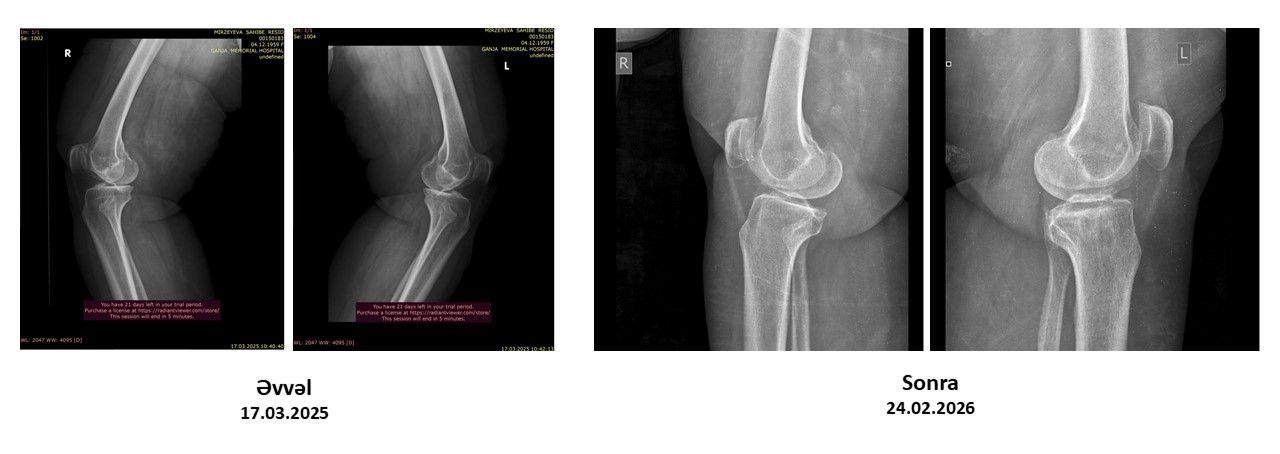

Protez təklif edildi, amma əməliyyatsız sağaldı –  Real pasiyent hekayəsi-VİDEO

Oynaqlarda yaranan artroz, xüsusilə də xəstəliyin 4-cü mərhələsi, tibbdə ən ağır vəziyyətlərdən biri hesab olunur. Bu mərhələdə xəstələrə əksər hallarda yeganə çıxış yolu kimi cərrahi əməliyyat – süni oynaq (protez) təklif edilir.

Lakin son illər bəzi klinikalarda tətbiq olunan inteqrativ yanaşmalar bu sahədə fərqli nəticələrin mümkün olduğunu göstərir.

Bioloji Təbabət İnteqrativ Müalicə Mərkəzinə müraciət edən pasiyentə 4-cü dərəcəli artroz diaqnozu qoyulmuşdu.

Pasiyent daha əvvəl müraciət etdiyi tibb müəssisələrində yalnız əməliyyatın mümkün çıxış yolu olduğu barədə məlumat almışdı. Güclü ağrılar, hərəkət məhdudiyyəti və gündəlik həyat keyfiyyətinin aşağı düşməsi onun əsas şikayətləri idi.

Nəticə: əməliyyata ehtiyac qalmadı

Aparılan müalicədən sonra pasiyentdə nəzərəçarpacaq müsbət dəyişikliklər müşahidə olunub:

• ağrılar əhəmiyyətli dərəcədə azalıb

• oynağın hərəkət qabiliyyəti yaxşılaşıb

• gündəlik fəaliyyətlər daha rahat icra olunmağa başlayıb

• həyat keyfiyyəti yüksəlib

Hazırkı vəziyyətdə pasiyent üçün cərrahi müdaxiləyə ehtiyac qalmadığı bildirilir.